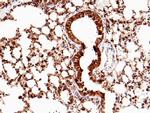

SFTPC Polyclonal Antibody

种属

Human Mouse Rat

类型

Rabbit Polyclonal

应用

WB IHC (P) ICC/IF Flow